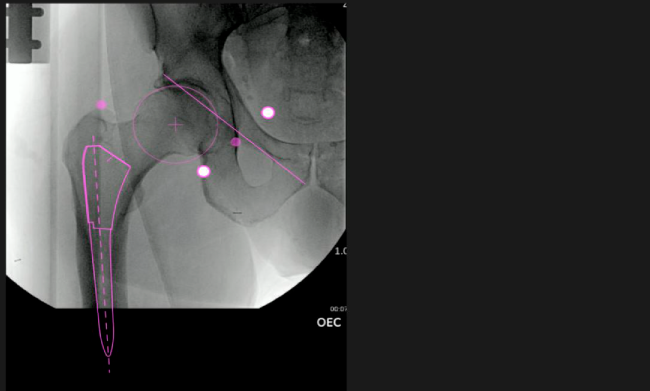

Planeación preoperatoria mediante la creación de plantillas digitales para reemplazo de cadera y análisis intraoperatorio

Mayor nivel de información intraoperatoria facilita la colocación correcta de los implantes:

• Inclinación y anteversión de la copa acetabular para una correcta colocación del implante.

• Desplazamiento y offset para posicionamiento óptimo del componente (vástago) femoral.

• Verificación de la posición deseada del implante que potencialmente puede ayudar a reducir la probabilidad de dislocación protésica y aumentar la estabilidad de la articulación.

• Anotaciones digitales y herramientas de análisis de longitud de pierna.

• Con tecnología ONETRIAL® que calcula automáticamente el cambio en la longitud de la pierna y el desplazamiento para todas las combinaciones de implantes en una tabla fácil de leer.